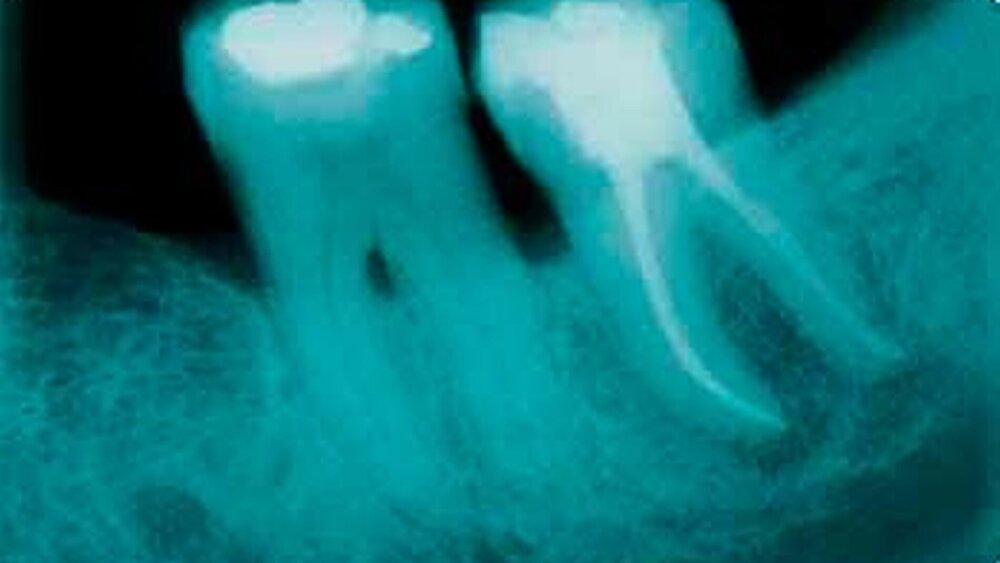

Bei beiden Fällen hatte sich der Knochen zirkulär nahezu vollständig abgebaut und die Zähne wiesen Lockerungsgrad III auf. Dass die Furkation bei Zahn 38 weit offen lag und durchgängig sondierbar war (Grad 3) kann schon bei genauer Betrachtung des Röntgenbildes (Abbildung 4) vom 15. Januar 2001 erkannt werden. Bis zum Tag der Wurzelbehandlung und Trans-Replantation, am 17. September 2001, hatte sich dieser Zustand nochmals deutlich verschlechtert.

Die Röntgenbilder des postoperativen Verlaufes (Abbildungen 2, 3, 5 und 6) zeigen die unerwartet eindrucksvolle Knochenregeneration bei gleichzeitig fehlenden Resorptionszeichen. Die Frage, ob sich ein neuer Parodontalspalt gebildet hat, kann röntgenologisch nicht eindeutig geklärt werden. Beide Zähne erscheinen ohne jeglichen Lockerungsgrad klinisch stabil, mit – bis auf 31 mesial – entzündungsfreien Taschen. Die Sondierungstiefen betragen zirkulär ein bis zwei Millimeter und nur an 31 mesial fünf Millimeter. Die Pflege des Patienten im Interdentalraum 31/41 ist mäßig bis schlecht, so dass dort eventuell von einem Rezidiv ausgegangen werden muss. Ansonsten sind sogar diese, auch von versierten Zahnärzten als hoffnungslos eingestuften Zähne bis zum heutigen Tage absolut fest und in der ihnen zugedachten Funktion.